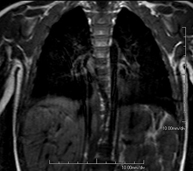

- RM Tórax

Prueba diagnóstica no invasiva que consiste en la obtención de imágenes de alta definición anatómica del tórax mediante el empleo de un campo electromagnético y ondas de radio (con un emisor y un receptor). No utiliza radiación ionizante. Está indicada en aquellas lesiones pulmonares en las que debe descartarse si existe infiltración del mediastino o de la pared torácica, para diferenciar si una lesión torácica es sólida o quística, etc. En ocasiones se deberá emplear contraste paramagnético (Gadolinio) para completar el estudio.